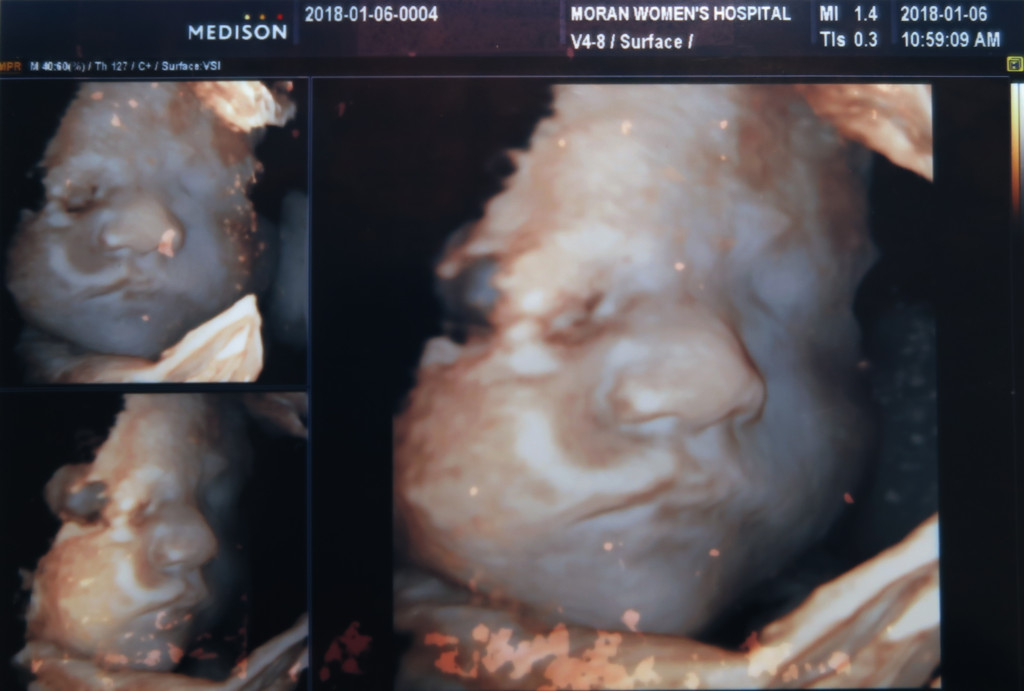

2차 정밀 초음파 사진은 얼굴 윤곽만 살짝 나오네요.

그래도 서현이때 보다 얼굴을 덜 가리고 있어서 이런 해골 사진도 남기고 ㅋㅋ

이때는 서현이랑 얼굴이 많이 비슷해 보이네요 ㅎㅎ

콧대는 서현이 보다는 조금 더 있는듯 하나…